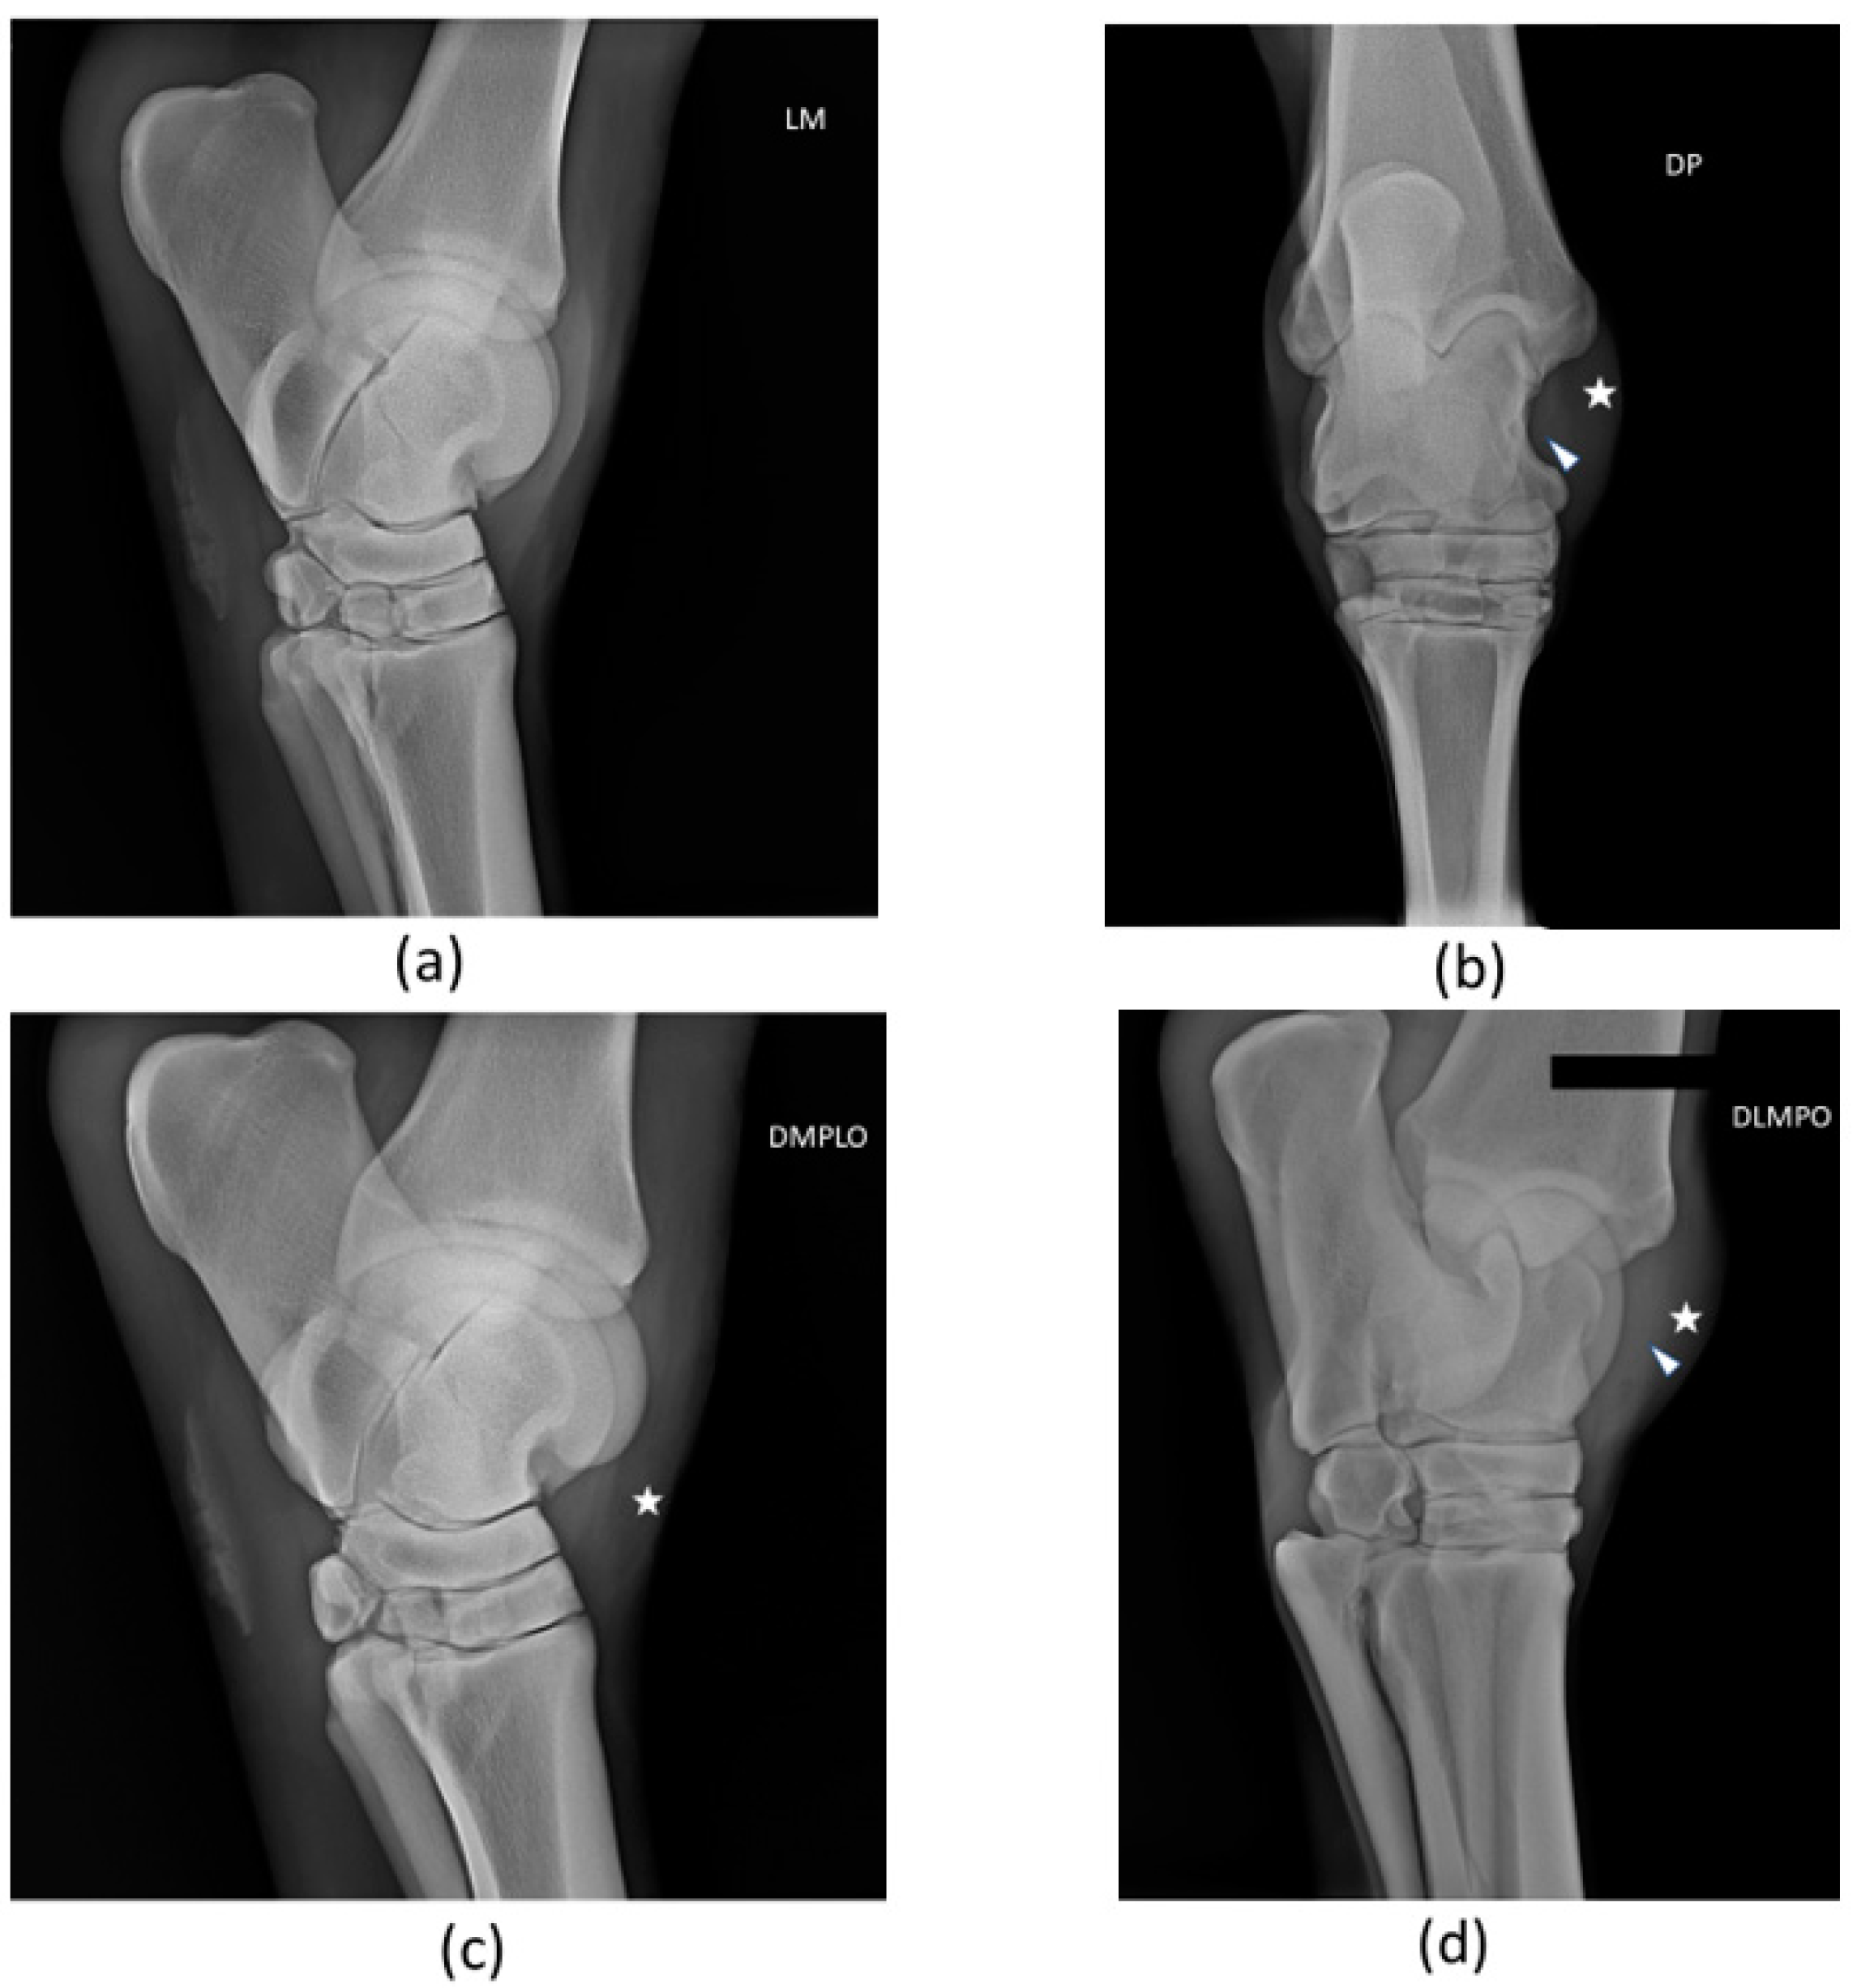

To sum up, the assessment of the patient’s clinical recovery was performed by the presence of no pain in the tarsus and no lameness achieved by day 30. Lesion ultrasonographic improvement and indicators of regeneration were evidenced by a progressive increase in echogenicity and fiber alignment, and decrease in ligament cross-sectional area and synovial fluid accumulation within the joint space, observed through ultrasound examination during the follow-up on days 1 (T0), 15 (T1), 30 (T2), 45 (T3), and 60 (T4) (Figure 8).

Figure 8.

Images of ultrasonographic follow-up. (a) Day 1 (T0), (b) day 15 (T1), (c) day 30 (T2), and (d) day 60 (T3). Indicators of ligamentous regeneration: increased echogenicity and fiber alignment, as well as decrease in cross-sectional area and synovial fluid accumulation within the joint space.

On day 30 (T2), there was no evidence of pain and lameness (grade 0/5). Ultrasonographic evaluation evidenced increased echogenicity of the lesion as well as a reduction in the cross-sectional area with good fiber alignment. The tarsocrural joint swelling and oedema were reduced. Nevertheless, compared with the contralateral limb, the right tarsocrural joint diameter was still larger than the left.

Over the course of the follow-up ultrasonographic examinations, an increasing echogenicity of the lesion was evidenced, as well as a reduction in the cross-sectional area, good fiber alignment, and a reduction of the abnormal synovial fluid. On day 60 (T4), two months after the first treatment, there was a complete recuperation of the ligament structure—lesion completely fulfilled, good echogenicity, good fiber alignment, and normal cross-sectional area—compatible with adequate tissue regeneration. No pain and no lameness were present, and there were also no signs of cartilage remodeling. Despite this achievement, a physical rehabilitation program proceeded until day 90 (T5).